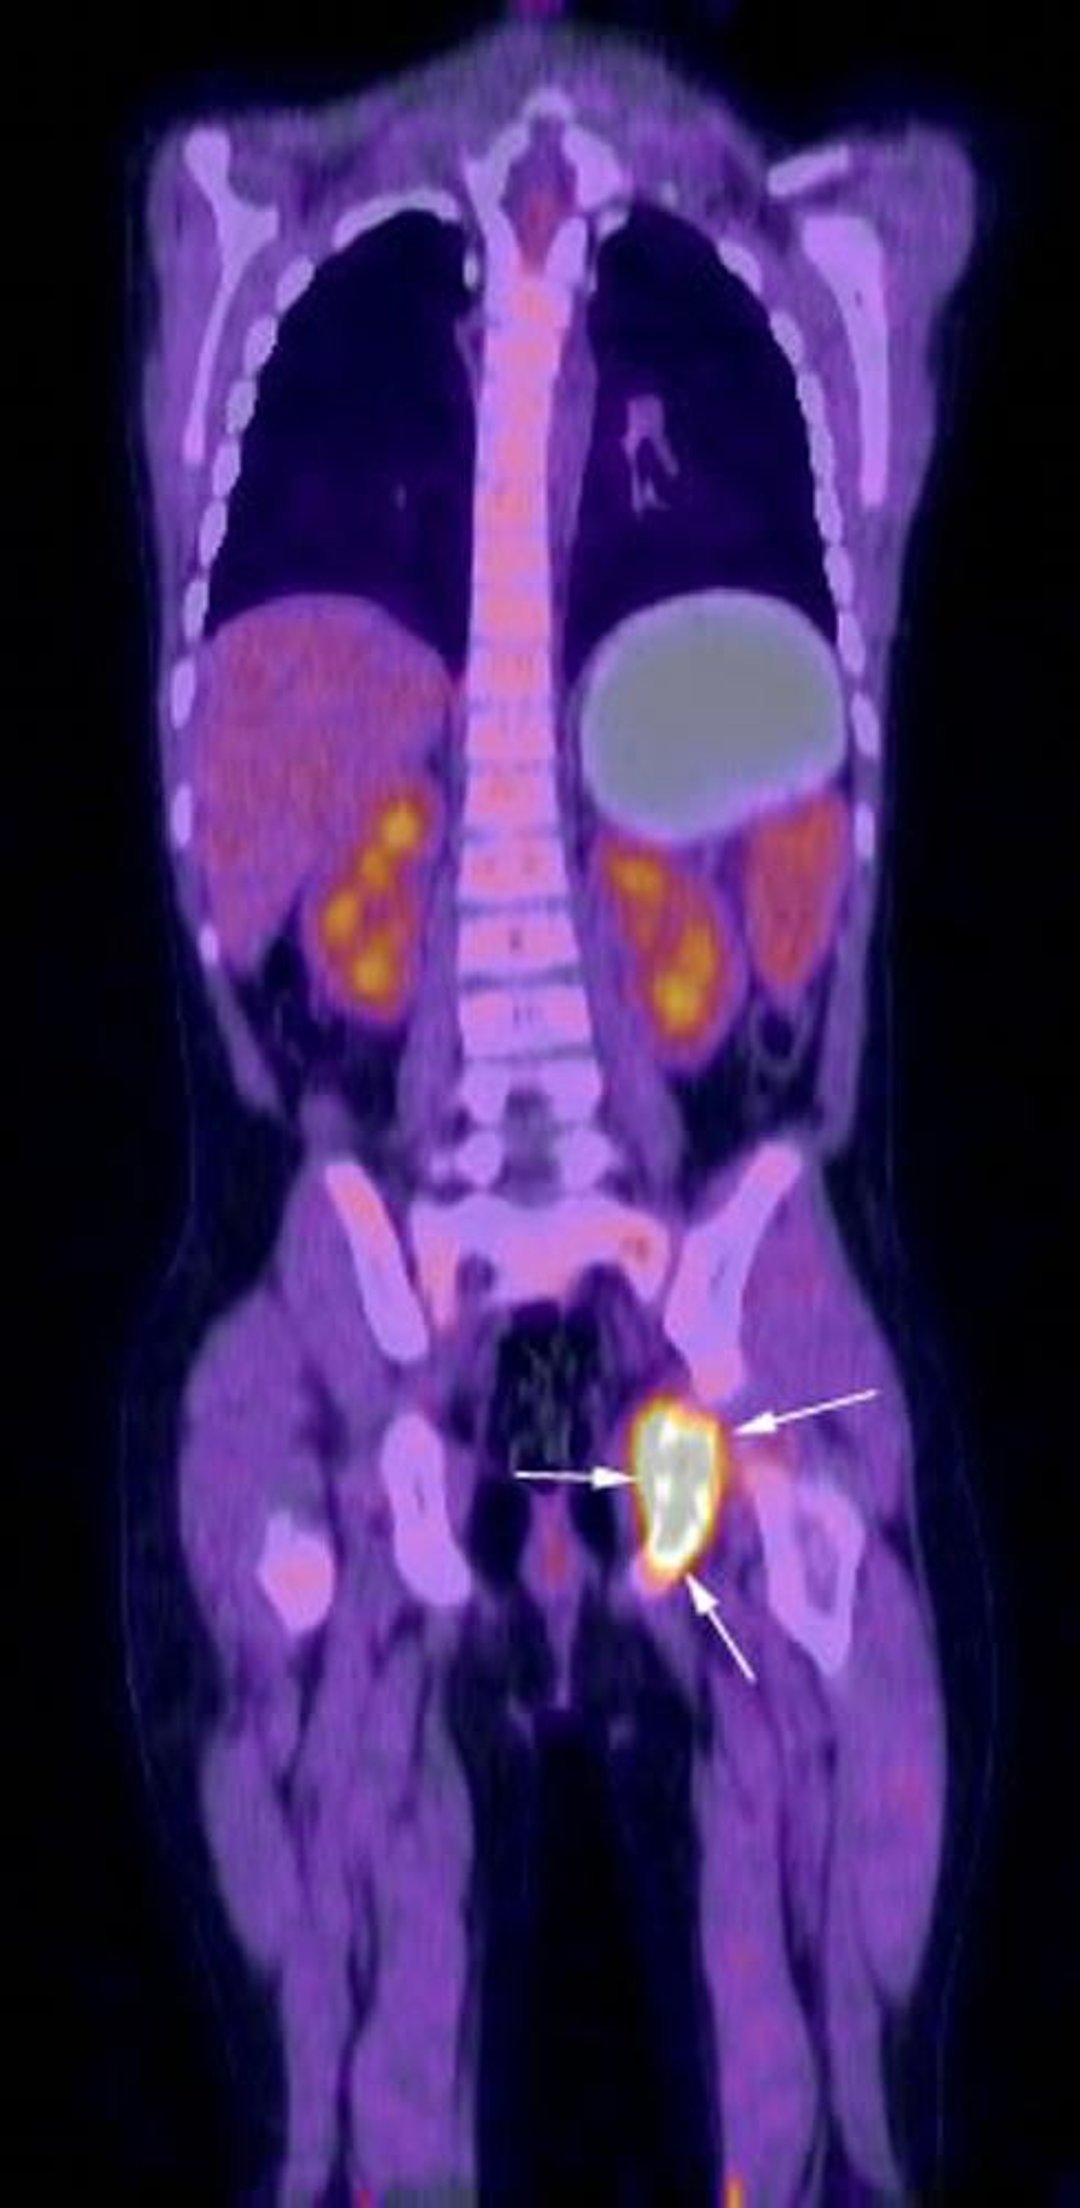

Imagem de reconstrução coronal do exame com PET-TC por FDG mostra intensa atividade metabólica na região do ísquio esquerdo (setas) correspondendo à histiocitose conhecida de células de Langerhans do paciente.

Imagem cedida por cortesia de Hakan Ilaslan, MD.